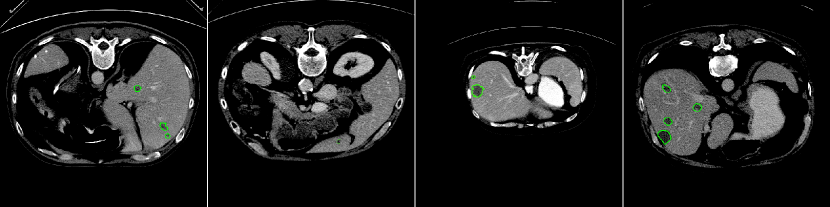

Experimental Results. Since we do not have the ground truth for the LiTS test set, we first perform the two-fold cross-validation on the training set to quantitatively and qualitatively evaluate the performance of our proposed method. We obtain Dice per case and some visual samples are presented in Fig. 6.

Observations on LiTS Annotations. As shown in Fig. 6, the LiTS annotations have both over-segmentation and under-segmentation issues. For the large lesions in both cases shown in Fig. 6, our predictions better fit lesions compared to the ground truth; while for the small lesions, our predictions locate more lesions potentially missing in the ground truth. Similar observations have been reported in [4]. Due to the imperfect ground truth provided by the LiTS challenge, we argue that the metrics computed against the ground truth probably could not be the only way to compare the segmentation results. Visual results could be considered as well and ours indicate the efficiency of our method.